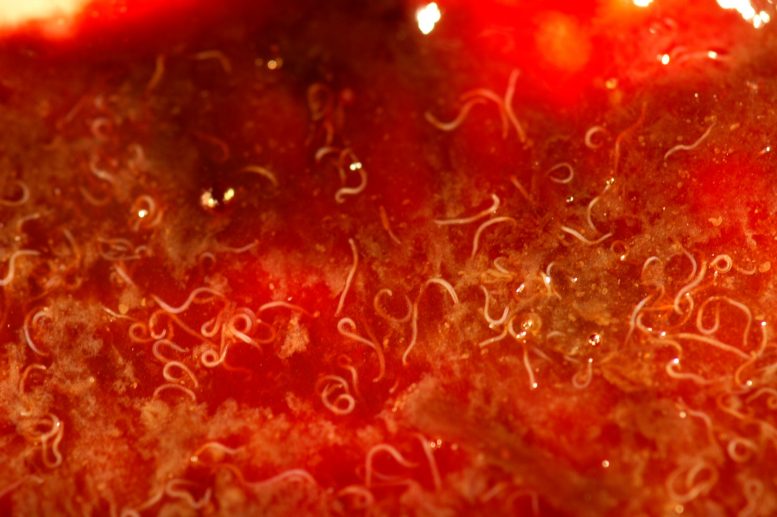

The hookworms are known to grab onto a dog’s intestines with their hook-like teeth and feed on tissue fluids and blood. The canines infected with hookworms show symptoms like significant weight loss, bloody feces, anemia, and lethargy. In some cases, it can also be fatal.

For their study, the researchers focused on racing greyhounds. Due to the sandy dirt of the facility, which is an ideal breeding environment for hookworms, dog racetracks are particularly favorable to the parasite’s spread. Due to the circumstances, all of the dogs are dewormed every three to four weeks.

The concern was that even after the dogs were treated for the hookworms, they still had significant levels of infection.

It has been noticed in the research that the parasites had evolved due to unusual mutations allowing them to survive deworming treatments. The researchers believe that if dewormers are continued on a regular basis, the newly mutated resistant worms will live and pass on the mutation to their progeny.